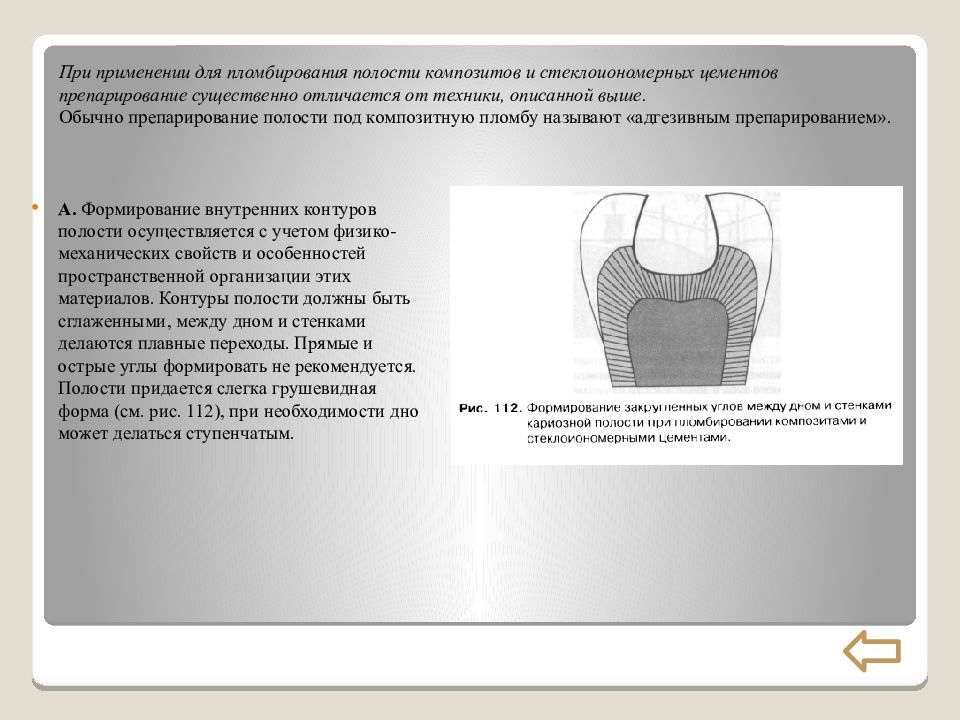

Препарирование кариозных полостей III класса: пошаговое руководство с фото